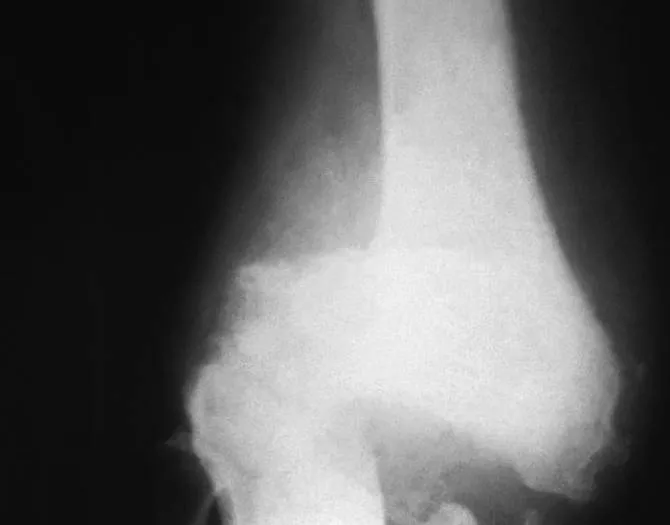

huesos